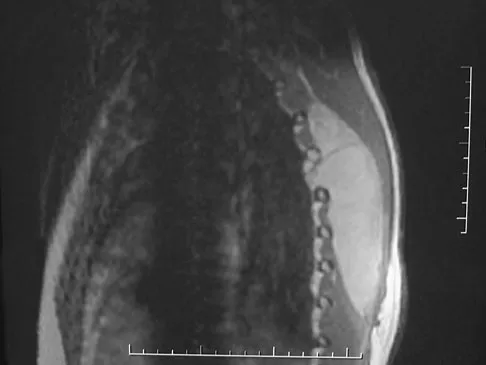

A 60-year-old woman with a history of breast cancer has progressive paraparesis. The MRI scan is shown in Figure 28. What form of management is most likely to restore or maintain ambulation?

Explanation